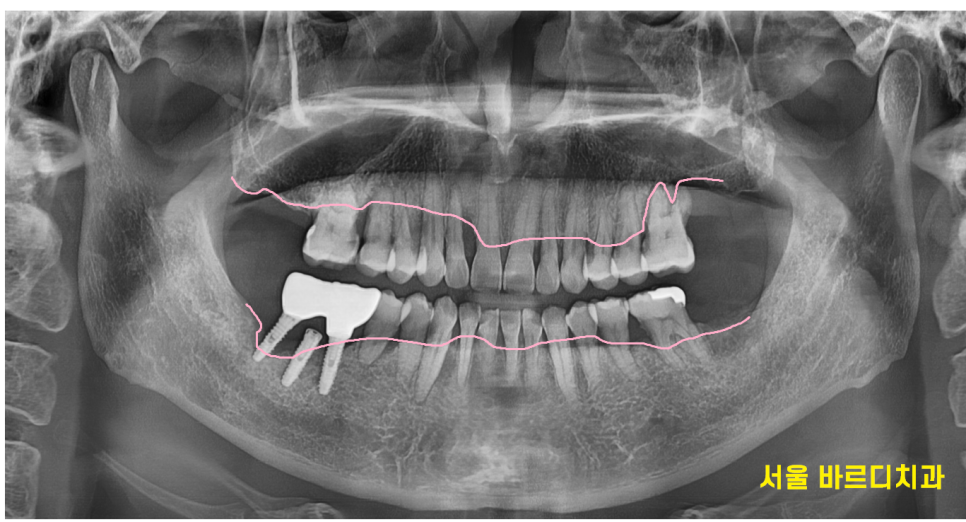

잇몸 뼈가 많이 녹은 x - ray를 보여드릴께요~

240430

계속 방치하면 치아가 잇몸에 대롱 대롱 매달려있는

거의 뿌리만 잡고 있는 형태가 됩니다.